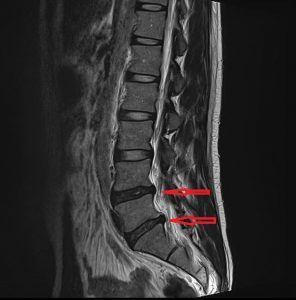

요추 추간판 탈출증 (요추 디스크)

요추 추간판 탈출증 (요추 디스크) 안녕하세요. 고래한의원 원장 박대명입니다. 오늘은 요추 추간판 탈출증, 흔히 말하는 허리 디스크에 대해 말씀드리겠습니다. ‘요추 추간판 탈출증’은 허리 통증과 함께 다리로 이어지는 저림이나 방사되는 통증을...